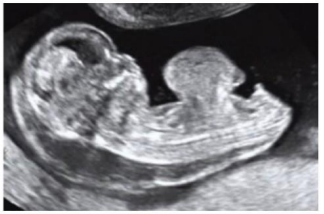

Uma paciente de 32 anos de idade, G1, compareceu à primeira consulta de pré-natal com 15 semanas de gestação. Tem história de conização há 2 anos por lesão de alto grau no colo uterino e miastenia grave. Faz uso de prednisona e azatioprina para controle da doença.